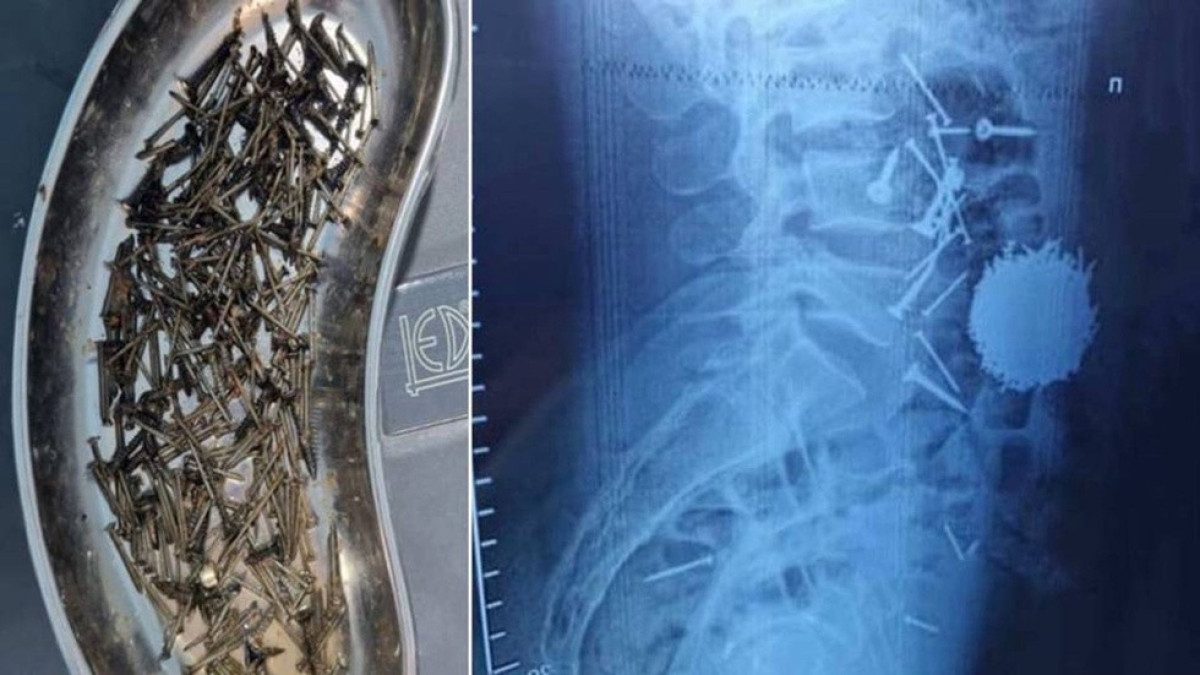

Самарқанд қаласында дәрігерлер науқасқа ота жасап, оның асқазанынан 200 грамм шеге мен бұрандалар алып шыққан.

Іші ауырған 29 жастағы науқас ауруханаға жеткізілген. Жедел қабылдау бөлімінде жүргізілген диагностика мен лабораториялық анализдердің нәтижесінде науқастың асқазан-ішек жолында бөгде заттар - тырнақтар, шеге мен бұрандалар бар екені анықталған.

Науқасқа шұғыл лапаротомия және гастростомия отасы жасалды. Науқастың ішінен шамамен 200 грамм металл заттары шықты. Операция шамамен бір сағатқа созылды. Қазіргі уақытта науқастың жағдайы жақсы, ол еркін қозғала алады, - деді дәрігер Йулдаш Қулиев.